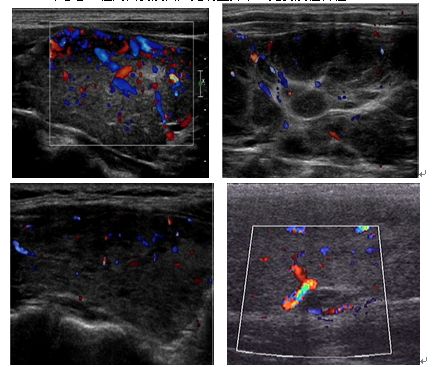

甲状腺结节可由多种病因引起,伴随吞咽而上下移动,包括甲状腺炎症、自身免疫、退行性变等都会出现结节。其中,单发结节甲状腺癌发生率更高,多发结节发病率更高。

3、结节性甲状腺肿

分泌TSH增多,体内甲状腺激素相对不足,结节内有钙化、出血、囊变,多见于中年女性。因为TSH分泌增多,进而导致甲状腺不均匀增大和结节样变。

临床最主要表现为甲状腺肿大,结节质地中等硬度,通过手术或者显象时,经常发现多个结节。患者甲功都正常,临床表现不多。